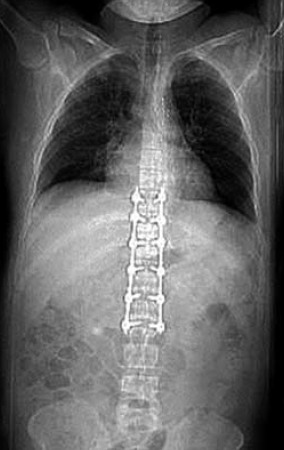

10. ábra.

A lumbalis gerinc rögzítése után az aorta laesio megoldását halasztottan végeztük.

Neurológiai vizsgálattal petyhüdt alsó végtagi paraplegia volt kimutatható. Tudata visszatért. 24 órán belül, keringési paramétereinek stabilizálása után, stent graft implantatiot, majd másnap ThX-LII segmentumban transpedicularis gerincrögzítést végeztünk (10.,11., 12. ábra). Paraplegia mellett lábszártörését egy héttel később lemezes osteosynthesissel oldottuk meg. A postoperativ szakban septicus szövődmények alakultak ki mind lágyrész sérüléseinek mind gerincműtétének területén. Hosszas antibiotikus kezelés mellett septicus állapota rendeződött. Parapareticus állapotban került vissza a beküldő kórházba rehabilitatio céljából. A betegek és ellátásuk adatainak összefoglalását I, II és III táblázat mutatja.